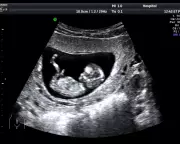

Anastasia Shubareva-Epshtein shares her traumatic experience of confirming a miscarriage in a London ultrasound clinic on Mother's Day, highlighting the lack of support for pregnancy loss.